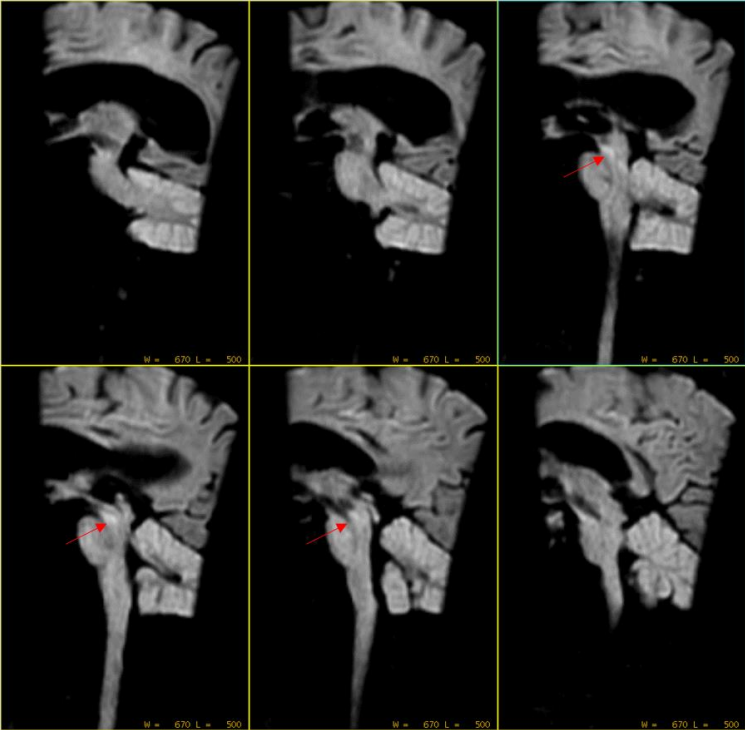

可见中脑位置似乎有异常稍高信号灶。但是患者开始出现运动。此时留给技术组老师的时间已经不多了。 然而,经过简单有效沟通后(扯着嗓子喊了一声:别动),扫描继续。 Sag DWI b=1000s/mm2,层厚3mm,0间隔扫描,扫描时间36秒: